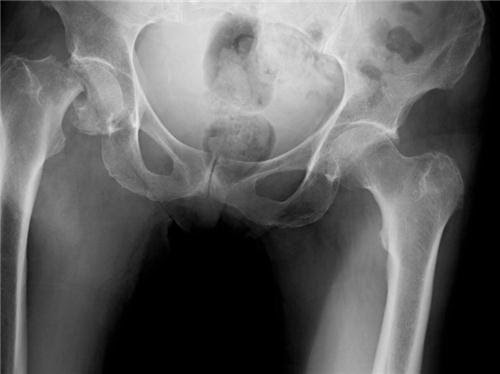

Xét đến vấn đề chủng tộc thì ở Mỹ, số phụ nữ da trắng bị gãy xương hông nhiều gấp đôi so với phụ nữ da đen. Có một số yếu tố được nêu ra nhằm lý giải việc khung xương phụ nữ da đen thì khoẻ hơn, trong đó có việc khối lượng xương cao hơn trong thời thơ ấu và tỷ lệ chu chuyển xương (bone turnover) thấp, từ đó có thể dẫn đến quá trình giảm mật độ xương theo tuổi tác của phụ nữ da đen chậm hơn so với phụ nữ da trắng.